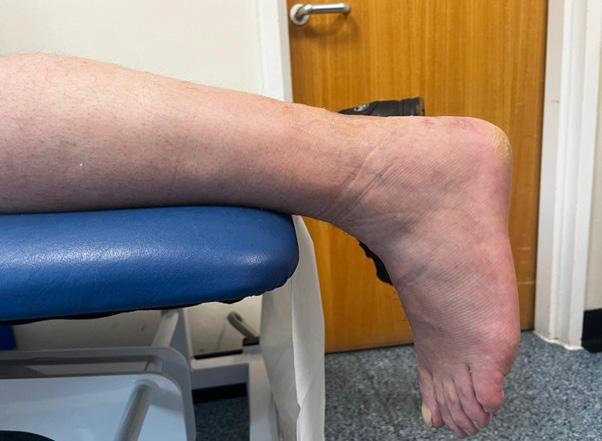

Posterior malleolar fractures (PMFs) account for up to 50% of ankle fractures when assessed with CT. The historical “one-third rule” guided fixation by fragment size; however, morphology and stability are now recognised as more important determinants of outcome.

Surgical fixation of PMFs is commonplace in unstable and displaced fracture patterns. Having spent the last decade researching PMFs, one of the most significant findings has been the importance of the correct surgical approach. Although the posterolateral (PL) approach remains common, in my practice it has been completely abandoned. Increasing evidence supports the medial posteromedial (MPM) approach in the exposure and fixation of PMFs, which has substantial benefits over the PL approach.

5. Positioning and Practicality

The MPM approach can be performed in a supine, semi-prone or prone position (figure 4). This simplifyss anaesthesia, allowing easier fluoroscopy and access to the anterior tibia if required. and enabling simultaneous fibular or syndesmotic fixation.

Recent CT-based studies have reported >90 % anatomical reduction within >>

2mm and >90 % syndesmotic congruity after MPM fixation, however other studies using PL approach only achieve approximately 50% anatomical reduction5, 6 Our own data has shown complication rates up to 66% following PL fixation, compared with 8% using MPM when using the Clavien-Dido classification for complications.

The MPM approach overcomes the three principal limitations of PL approach, restricted exposure, unaddressed entrapment, and vascular risk. Its direct vision of the posterior and medial tibia enables true anatomical reduction, particularly in die-punch and 2B PMFs. The ability to clear PTT entrapment prevents secondary displacement and pain. Preservation of the posterior vasculature markedly decreases complication rates. Adoption requires anatomical familiarity, but reproducibility and outcomes justify its broader implementation. In my view, due the vascular risks of the PL approach specific to a two-vessel limb, continued use of the PL approach should instigate a CT angiogram pre-surgery.